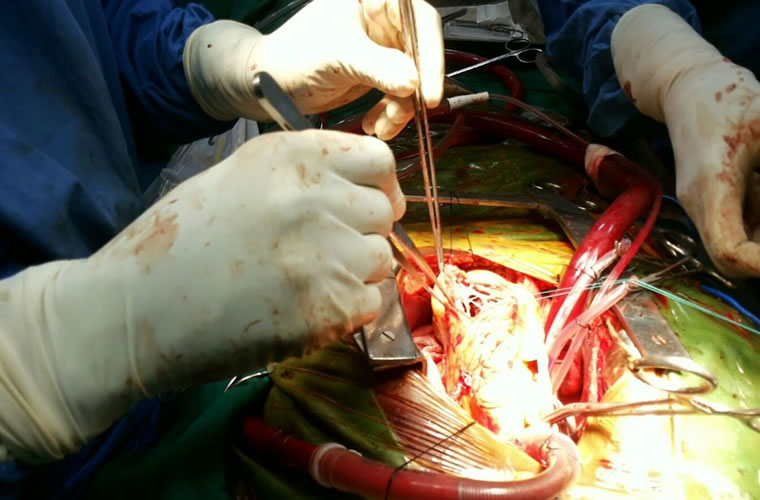

Dr.DineshShanmugaSundaram is specialized himself in each & every part of Cardiovascular & Thoracic Surgery both in Adult & Paediatric or Congenital Heart Diseases. He is both an ethical & academic surgeon,changed the trend in Cardiac Surgery to fast & safe level, as prolonged procedures in Cardiac Surgery increases postoperative complications. We aim at decreasing perioperative complications to the maximal level. Read More